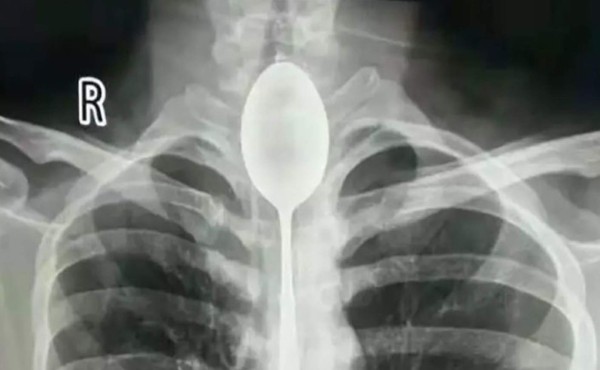

El hombre, de apellido Zhang, llegó al Hospital General de Xinjiang con dolores en el pecho y los doctores se sorprendieron al conocer que llevaba con la cuchara ahí por un año.

Los doctores quedaron impactados por el caso y admitieron que nunca antes habían visto algo similar. Sostuvieron que cuando recibieron al paciente, su esófago 'ya estaba infectado'.